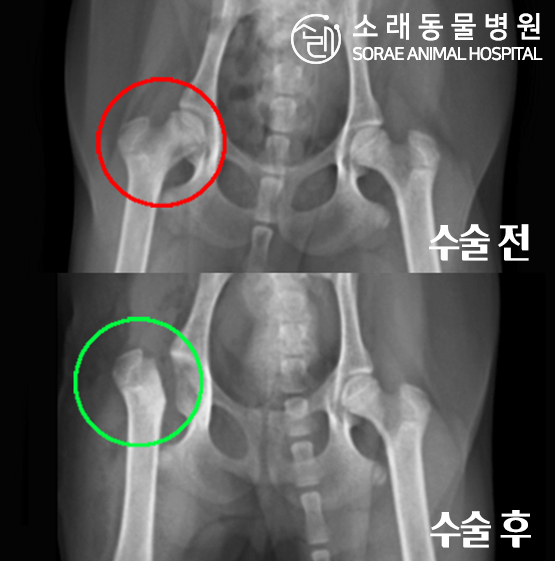

레오는 우측 뒷다리를 저는 파행 증상으로 내원하였습니다.

촉진 및 방사선 촬영 결과 대퇴골두허혈성괴사(LCPD)로 확인되어

대퇴골두 절골술(FHNO) 수술이 필요하다고 판단되었습니다.

문제의 원인이 되는 대퇴골두를 깔끔하게 절단해 주었습니다.

수술 전과 수술 후 촬영한 고관절 방사선 사진입니다.

대퇴골두가 깔끔하게 절단된 것이 확인됩니다.

이제 재활 운동을 통해 체중을 지지할 근육을 키워주게 됩니다.